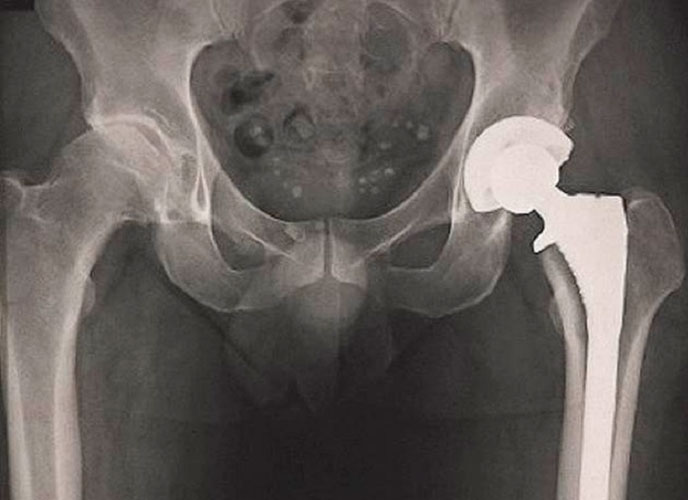

A inspeção radiográfica de componentes metálicos dos implantes para cirurgia

Como deve ser realizada a inspeção radiográfica realizada por terceira parte? Quais são os mecanismos de absorção? Quais são os instrumentos de melhoria de imagem? O que deve ser feito em relação à qualidade da radiografia e interpretação radiográfica? Essas indagações estão sendo exibidas na NBR 15892 de 10/2022 - Implantes para cirurgia - Requisitos e orientações para procedimento e inspeção radiográfica de componentes metálicos.

A NBR 15892 de 10/2022 - Implantes para cirurgia - Requisitos e orientações para procedimento e inspeção radiográfica de componentes metálicos estabelece os requisitos e as orientações para o procedimento e a inspeção radiográfica de componentes fabricados por materiais metálicos fundidos e por soldagens de reparação destinados ao uso em implante para cirurgia. Inclui procedimentos para a inspeção por métodos computadorizados e digitais e os requisitos deste documento objetivam estabelecer controles para a qualidade da imagem radiográfica de implantes para cirurgia metálicos fundidos e de soldagens de reparação associadas. Quando não especificado de outra forma, o termo fabricante se refere ao fabricante de implante e o termo implante se refere ao implante para cirurgia metálico fundido ou ao componente do implante para cirurgia metálico fundido.

O ensaio não destrutivo por imagem de raio X é um método alternativo para avaliar aspectos macroscópicos internos da estrutura de implantes cirúrgicos metálicos fundidos, bem como de componentes fundidos submetidos a soldaduras para reparo de falhas da fundição. Os critérios de aceitação para a inspeção radiográfica de implantes cirúrgicos metálicos fundidos e de soldagens de reparação são baseados em limites para imperfeições internas estabelecidas no projeto de desenvolvimento do componente e em imagens radiográficas de referência.